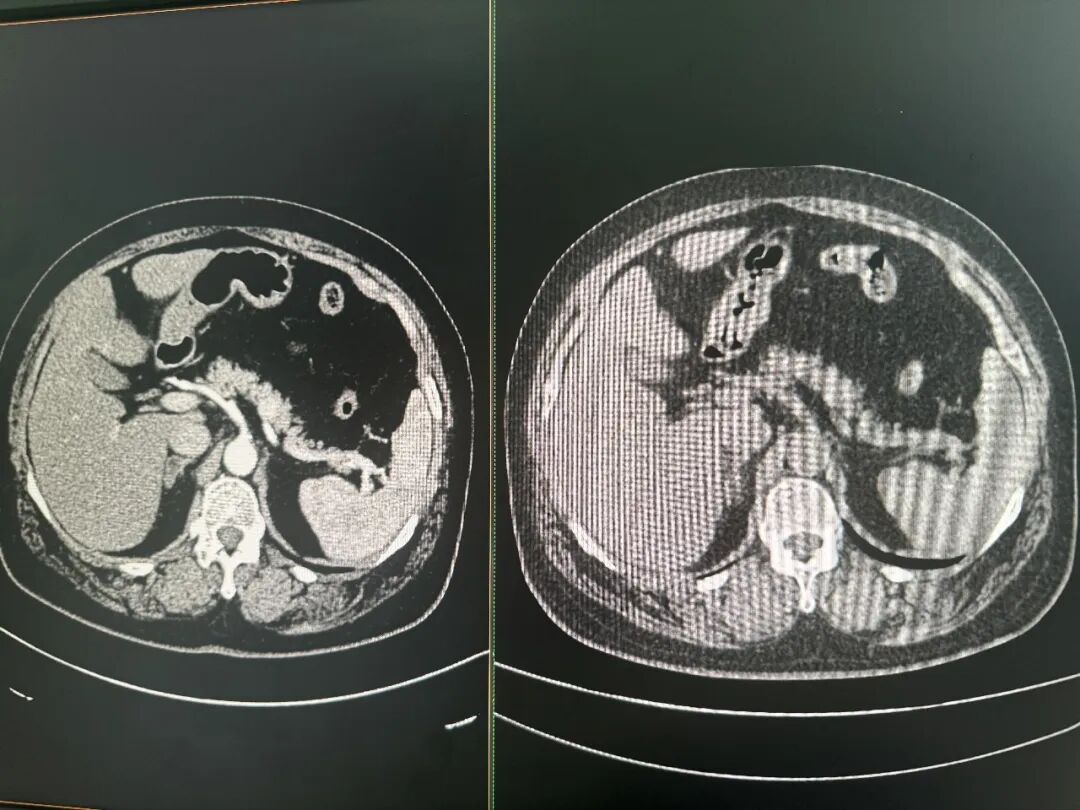

增强CT(左)和平扫CT(右)对比图

图片来源:每经记者 郑雨航 摄